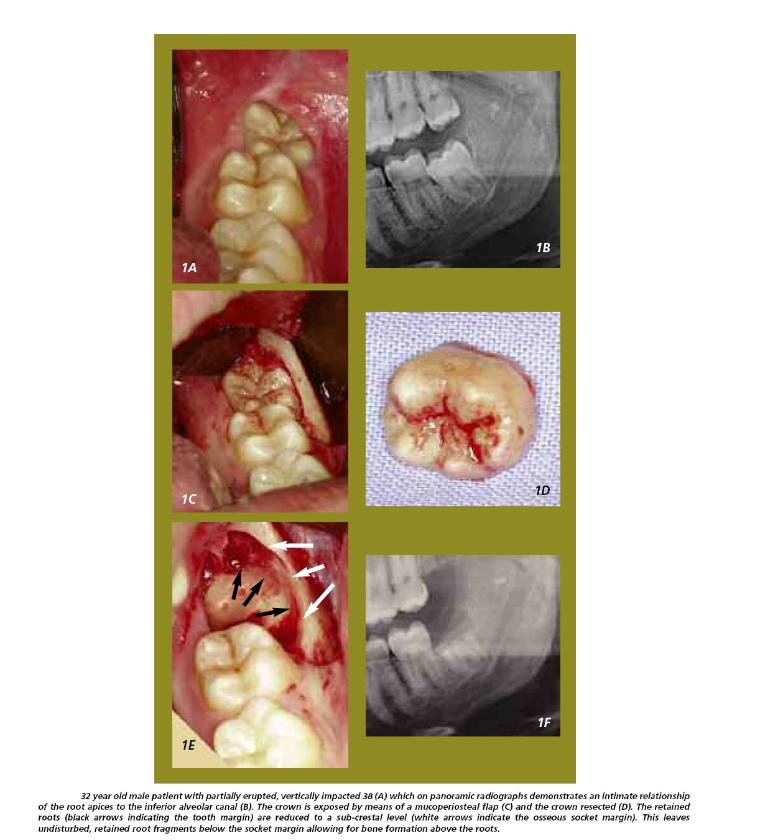

Coronectomy is the removal of the crown of a tooth, leaving the roots in situ.

When applied to a lower wisdom tooth or any lower unerupted posterior tooth, it is a procedure used to avoid damage to the Inferior Alveolar Nerve (IAN) (the nerve that supplies feeling / sensation to the lip and chin) when the X-ray has suggested an intimate relationship between the roots of the lower wisdom tooth and the IAN (the intimacy of the tooth roots to the nerve canal can be confirmed with the use of a Cone Beam CT scan [CBCT]).

The expectation, after removing the top of the tooth, is that the roots will remain in place and eventually sealed with bone.

Subsequent migration of the roots away from the IAN occurred in 14 – 81% of cases. The roots seem to move the most during the first 6 months post-coronectomy, with a typical distance of 2 – 3mm away from the IAN. Root migration halts as the bone regenerates and remodels.